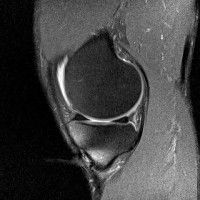

무릎 mri 간단히 봐주실 수 있으시나요 ㅠㅠ

안녕하세요 8년전 십자인대 수술하고 최근 무리한 운동에 무릎 불편감이 생겨서

mri 찍었습니다.

진단결과는 첫 찍은 병원에서 활액막염 이라는 진단을 받았습니다. 혹시 봐주실 수 있으실까요?

올라온 MRI가 단편적이라서 정확한 진단에 어려움이 있지만 십자인대에는 큰 이상이 있지는 않은것 같으며, 무릎관절내 물이 있는 것으로 보아 활액막염의 진단이 맞을 것 같습니다.

하지만 단편적인 영상이기 때문에 촬영병원에서 정확한 판독지 등을 받으시는 것이 좋겠습니다.